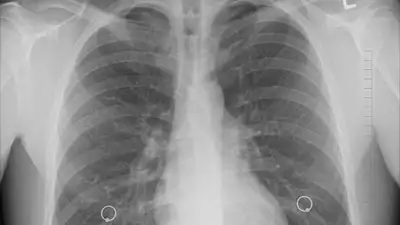

В Британии начались испытания первой в мире мРНК-вакцины для лечения рака легких, которая может стать альтернативой химиотерапии, поскольку представляет меньше вреда для организма, сообщает Zakon.kz.

"Первый пациент в рамках испытаний уже получил новую вакцину на основе технологии мРНК, предназначенную для уничтожения наиболее распространенной формы заболевания и предотвращения его рецидива. Препарат, разработанный германской биотехнологической компанией, стимулирует иммунную систему распознавать патологические клетки и бороться с ними", – говорится в сообщении.

Также отмечается, что исследуемая вакцина не имеет такого токсического воздействия на организм, как химиотерапия, которая часто поражает не только раковые, но и здоровые клетки.

"Мы надеемся, что [разработанная вакцина] даст возможность улучшить результаты лечения наших пациентов с немелкоклеточным раком легких как на ранних, так и на поздних стадиях", – отметил профессор Сиоу Минг Ли, возглавляющий исследование препарата в Британии.

Всего в испытаниях примут участие порядка 130 человек на исследовательских площадках в семи странах.